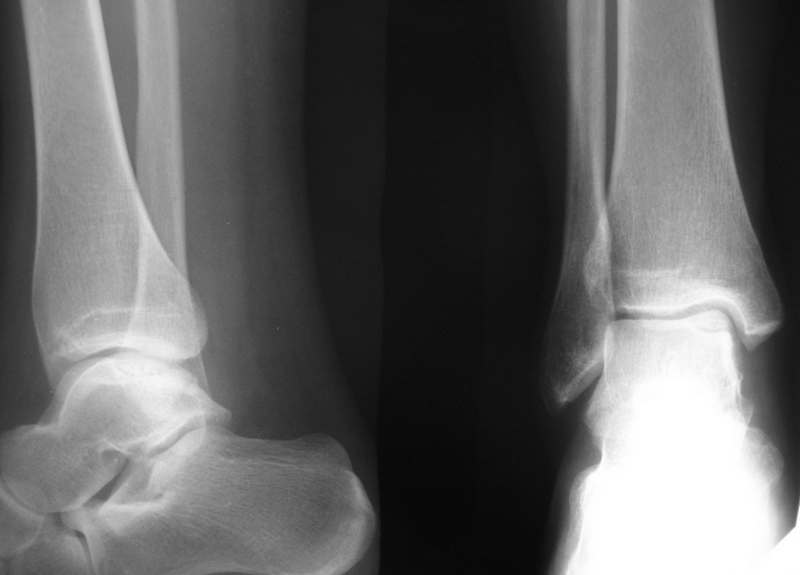

Остеохондропатия таранной кости

Больная М., 30 лет, около полугода беспокоят боли в голеностопном суставе.

На рентгенограммах и КТ признаки остеохондропатии блока таранной кости.(РКТ на бумаге поэтому не выкладываю)

Выносится на обсуждение тактика: 1. Просто ждать, назначив разгрузку сустава, физиолечение, ЛФК.

2. Артротомия сустава, фиксация винтом типа Герберта.

3. Артроскопия или артротомии с удалением фрагмента.